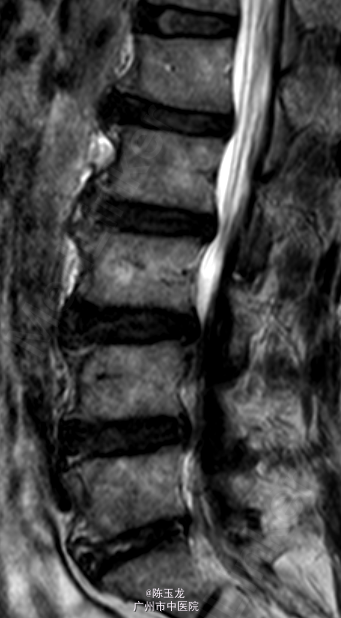

体查:腰椎活动稍受限,腰部有明显叩击痛,左小腿外侧区域感觉减退;双侧直腿抬高试验(—)。 辅助检查:三大常规、血生化、肝肾功能未见明显异常。腰椎MRI示:L4/5椎间盘突出。图片如下。

诊断:腰椎间盘突出症 处理:入院后完善相关检查,经专家组讨论,拟行手术:椎间孔镜下L4/5椎间盘摘除+射频消融术。